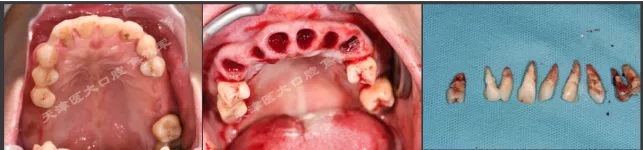

上颌即刻种植即刻修复手术过程

· 上颌360数字化序列导板+预成临时修复体

· 拔除部分牙齿,翻瓣,利用剩余牙齿支持组合导板,辅助基部导板就位固定,基部导板上缘做为去骨线,精确去骨。

· 全程导板就位,引导种植体植入,安装复合基台。

· 种植体植入位置偏腭侧,唇侧骨量过于丰满,上颌骨前突,去骨修整骨边缘。

· 口内pick-up 固定临时修复体,患者上下颌咬合关系良好。